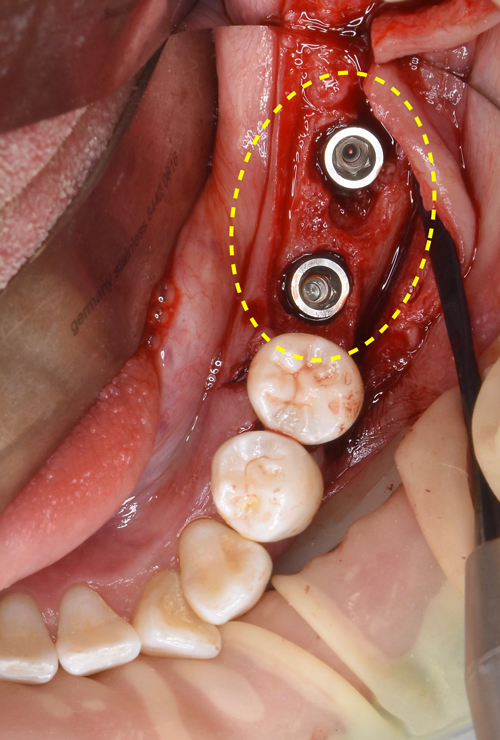

患者様は、迷わずインプラントを選択されました。抜歯と同時にインプラントの移植と自己血液を用いた骨の造成再生術を行われました。

腫瘍が骨を大きく溶かしていましたので、欠落した部分にCGFに人工の骨を混ぜ合わせ、骨の再生をインプラントの移植と同時に試みました。

手術直後の状態です。

インプラントの植立後、骨の不足している所には、自己血液を用いた骨の再生治療でバックアップします。

〈向かって右〉

骨の厚みを2倍に増幅させる「骨幅拡大手術(スプリットクレスト法)」を行なってからインプラントを移植した後、骨の厚みを確実にするために骨の再生治療も同時に行いました。

使用インプラント:ノーベルバイオケア社製 アクティブ直径3.5㎜ × 長さ13㎜ と 直径4.3㎜ × 長さ11.5㎜